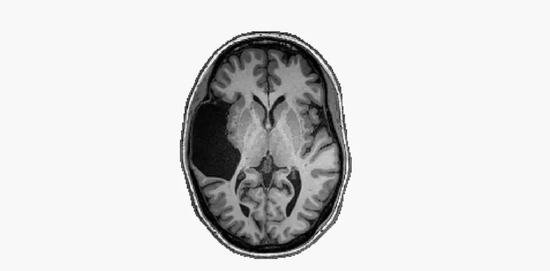

她缺少的脑区是左颞叶(left temporal lobe)。对大多数人来说,这是承载语言功能的一个关键区域,而她脑中的相应位置,有的只是脑脊液。曾经有位医生认为,她的词汇量不会超过五年级的小学生,但事实上她的言语智商(verbal IQ)测试成绩在人群中排到了前2%。不止如此,母语为英语的她,还熟练掌握俄语这门外语。

假如你还记得,本文主人公EG丢失的正是左脑的颞叶。可是她的语言能力并无明显缺陷,甚至还优于常人(除了拼写容易出错)。所以,科学家十分珍惜这个找上门来的案例。

结果,研究团队并没有在EG的左额叶发现语言活动,而右脑的额叶语言区与颞叶语言区都在工作。科学家由此推测,同一个半球存在颞叶,是产生额叶语言区的必要条件。在EG左颞叶缺失的情况下,即便左右脑的额叶之间相互连接,左额叶也无法借此获得语言功能。

EG的额颞叶语言网络,全部由她大脑的右半球提供。这也表示,一个半球就足以保障她完好的语言功能了。